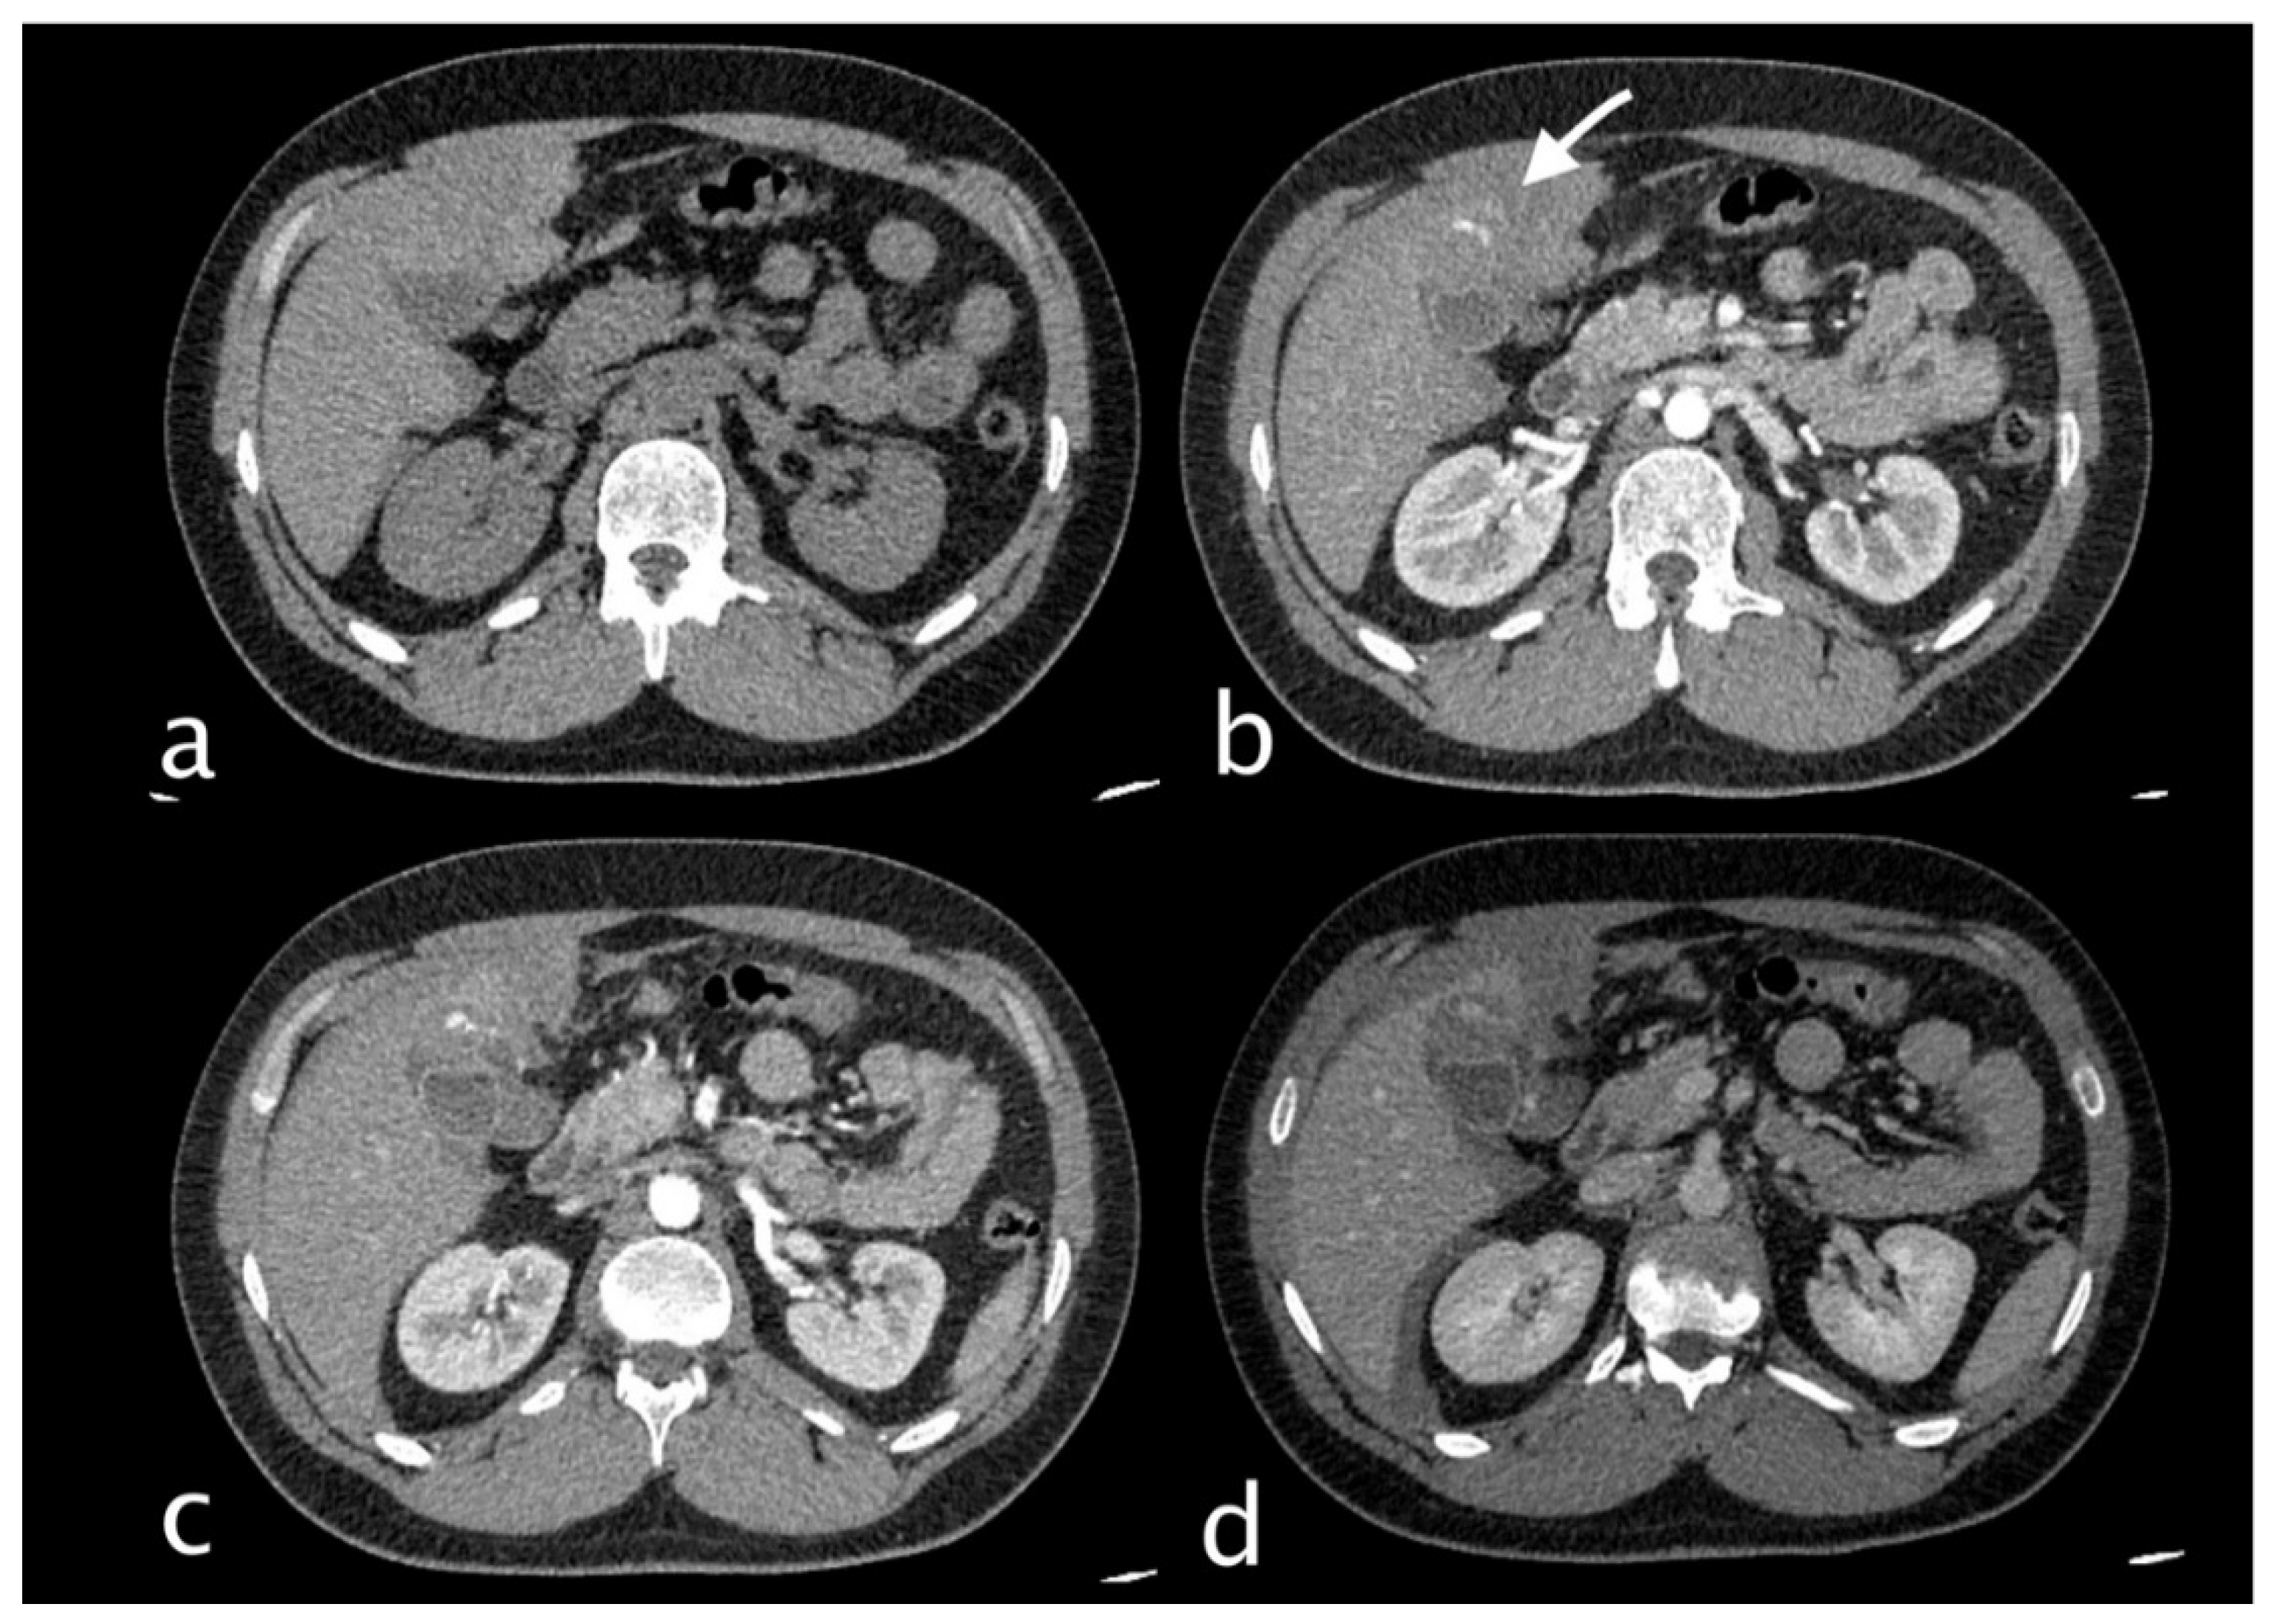

Figure 7.

58-year-old man hospitalized who underwent more than once ERCP for choledocholithiasis. He complained of severe right upper quadrant pain and sudden decline of Hb 7,3 g/dl (PCR 10,82 mg/dl, n.v. 0.0-0.5; WBC 18,76 103/mm3 n.v. 4.2-10.5). He underwent abdominal CT with IV contrast (a non-contrast, b arterial, c venous, d delayed phase), which showed dilated intrahepatic bile ducts and markedly dilated common bile duct that present inhomogeneous content and air bubble for previous procedure and sphincterotomy. Within the common bile duct a cystic artery pseudoaneurysm was detected with active extravasation. (white arrow). The patient underwent TAE successfully.